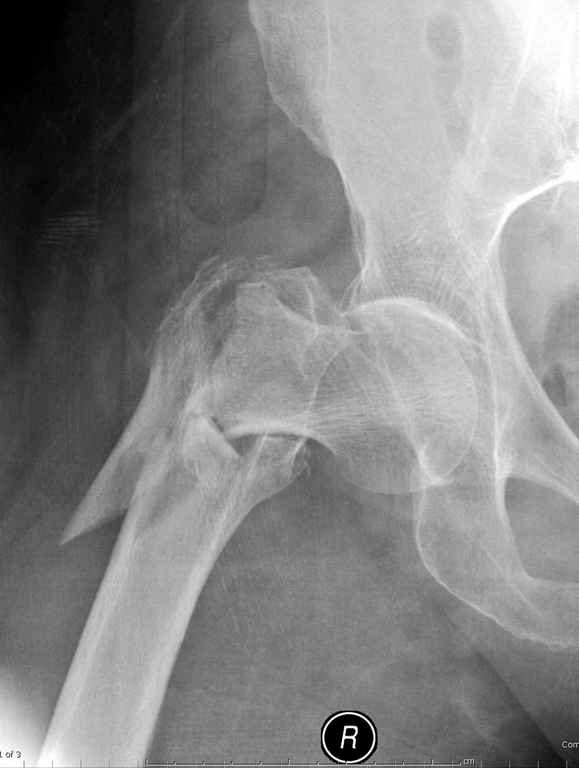

Re: оскольчатый чрезвертельный перелом

Предугадать распространение линий перелома при чрезвертельных и оскольчатых переломах трудно, поэтому для принятия правильного решения рекомендуется Компьютерно Томографические исследование.

При отсутствии КТ, снимок на вытяжении поможет увидеть общую картину расположения отломков, особенно потенциальные места введения импланта. Риск раскола в этом случае огромный, поэтому больной должен быть дообследован.

Здесь пара похожих случаев.